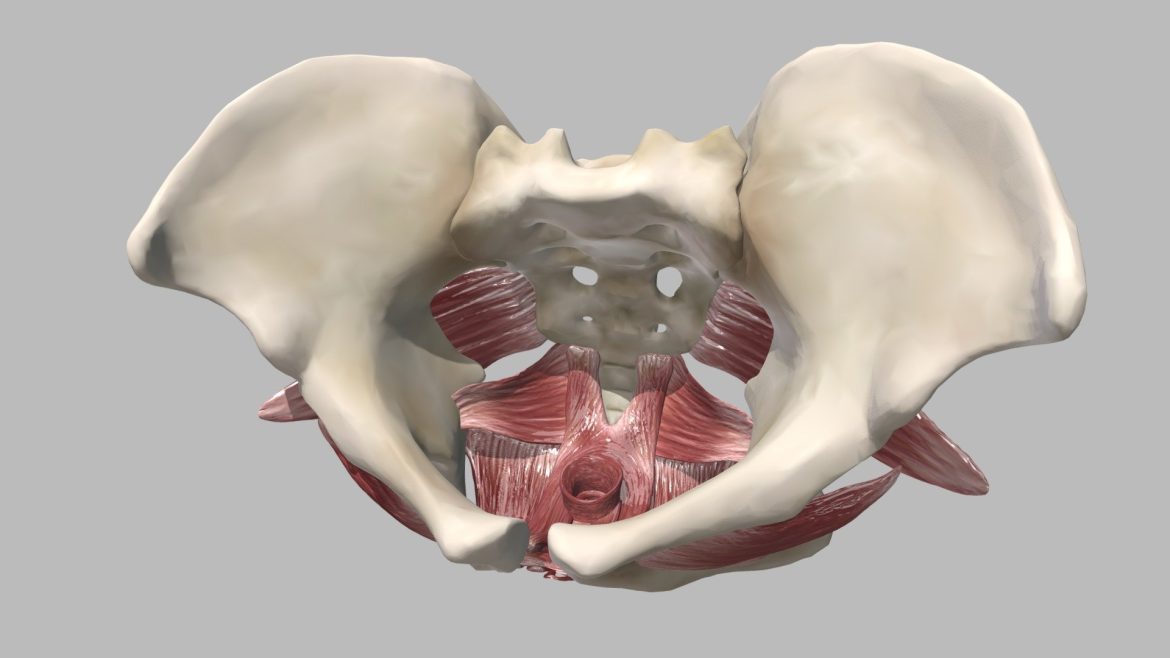

Female Floor Muscles 3d Model

Female Floor Muscles 3d Model – Unveiling Anatomical Precision

This meticulously rendered model stands as a testament to the fusion of artistic skill and scientific rigor. Created for the Centre for Anatomy and Human Identification at the University of Dundee, it represents a core component of an MSc Medical Art curriculum. Every curve, fiber, and attachment point reflects extensive research and a deep understanding of human anatomy, ensuring its value as a reliable educational tool.

Artists sculpted, textured, and colored each minute detail using ZBrush, achieving a level of realism essential for medical education. This digital recreation allows educators and students to explore the muscle groups, their spatial relationships, and their individual contributions to pelvic support and function with incredible fidelity. The precise coloration differentiates various structures, enhancing visual comprehension.

Educators continually seek innovative ways to teach complex anatomical concepts, and this 3D model provides an ideal solution. It serves as an invaluable resource for medical students, physical therapists, and researchers, offering an interactive alternative to traditional textbooks and static diagrams. Users rotate, zoom, and inspect the pelvic floor from any angle, gaining insights impossible with two-dimensional representations.

Understanding the pelvic floor’s multifaceted role in continence, support, and sexual health requires a clear visual aid. This model bridges the gap between theoretical knowledge and practical application, empowering learners to grasp the nuances of this vital muscular diaphragm. It facilitates a deeper engagement with the subject matter, ultimately leading to improved retention and application of knowledge.

This medical art piece not only demonstrates anatomical accuracy but also showcases the power of digital sculpting in the field of scientific illustration. It transforms abstract biological concepts into tangible, explorable forms. The dedication to detail ensures that every aspect of the musculature contributes to a comprehensive and correct representation.

The model’s design thoughtfully incorporates key visual and technical aspects:

- Detailed representation of the levator ani and coccygeus muscles.

- Accurate depiction of muscle origins, insertions, and fiber directions.

- Realistic texturing and anatomical coloration for clear differentiation of structures.

- Optimized mesh for smooth interactive viewing across various platforms.

Beyond academic study, this sophisticated anatomical model holds significant potential for clinical applications. Healthcare professionals utilize it for patient education, helping individuals visualize and understand their own anatomy during discussions about pelvic floor dysfunction, therapy, or surgical procedures. It empowers patients with knowledge, fostering better communication and treatment outcomes.

Acquire this exceptional digital asset to elevate your anatomical studies or integrate it into advanced e-learning modules. The female pelvic floor muscles 3d model offers an unparalleled opportunity to explore and comprehend this crucial part of human anatomy with precision and clarity. For an even deeper dive into this fascinating subject, you can learn more about the human pelvic floor. For other high-detail models, consider checking out our Teapot from Russia (USSR).

Seller Original Description

A study of the female pelvic floor muscles sculpted, textured and coloured using ZBrush.This piece was created as an e-learning resource for the Centre for Anatomy and Human Identification at the University of Dundee, and was submitted as part of the MSc Medical Art course at the university.

| 3D Model formats | FBX, OBJ, BLENDER, TEXTURES, Materials |

| 3D Model details | VR / AR / Low-poly, Textures, Materials, UV Mapping, Scale transformations |

| Triangles | 436.6k |

| Vertices | 217.8k |